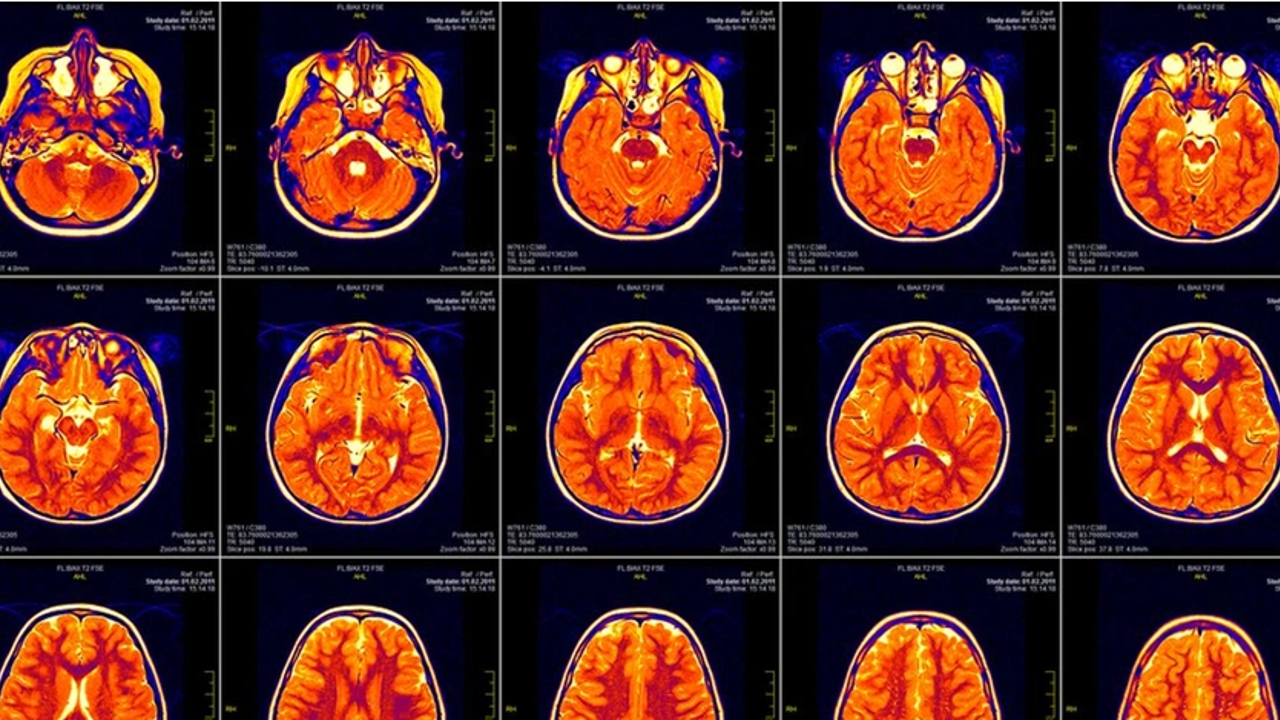

Beynin “normal” sıcaklığı, insanlarda hiçbir zaman tanımlanmadı. Bunun yerine, genellikle vücudun geri kalanıyla aynı olduğu varsayıldı. Önceki çalışmalar, beyinleri doğrudan izlenen beyin hasarlı hastalardan alınan verileri kullanmıştı. Artık beyin sıcaklığı, invaziv olmayan bir beyin tarama tekniği olan manyetik rezonans spektroskopisi (MRS) kullanılarak sağlıklı insanlarda ölçülebiliyor.

İnsan beyninin ısısı ölçüldü - Resim : 1

Yeni çalışmanın arkasındaki ekip, MRS''yi kullanarak 20 ila 40 yaşları arasındaki 20 erkek ve 20 kadın olmak üzere40 sağlıklı insanın beynini inceledi.Ölçümler bir gün boyunca üç kez alındı, bu da MRS''nin gün boyunca beyin sıcaklığındaki değişiklikleri izlemek için ilk kez kullanılmasına neden oldu.

Beyin sıcaklıkları 36,1°C ile 40,9°C arasında değişiyordu.Beyin yüzeyi daha soğuk olma eğilimindeyken, daha derin bölgelerin büyük ölçüde daha sıcak olduğu bulundu. Örneğin, beynin en derin bölgelerinden biri olan talamus, en yüksek sıcaklığın kaydedildiği yer.